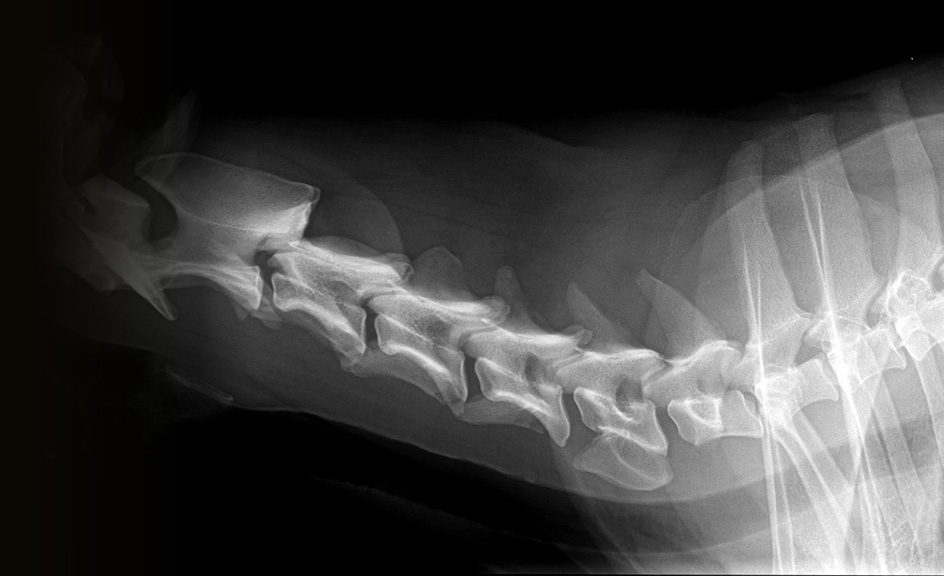

Die verwendete Csl-Szintillator Ausführung hat eine sehr hohe Belichtungsbandbreite womit auch mit wenig Dosis gute Röntgenaufnahmen gemacht werden können. Die Auflösung des drahtgebundenen Detektors beträgt ca. 4 Linienpaare pro mm (LP/mm) und hat damit auch bei kleinen Patienten eine sehr gute Detailzeichnung. Die Bildfläche des Detektors beträgt 43 x 43 cm bei äußeren Abmessung von 46 x 46 x 1,6 cm. Alternativ ist auch eine Wireless Variante verfügbar, je nach Ausführung, auch bis 5 Linienpaare/mm.